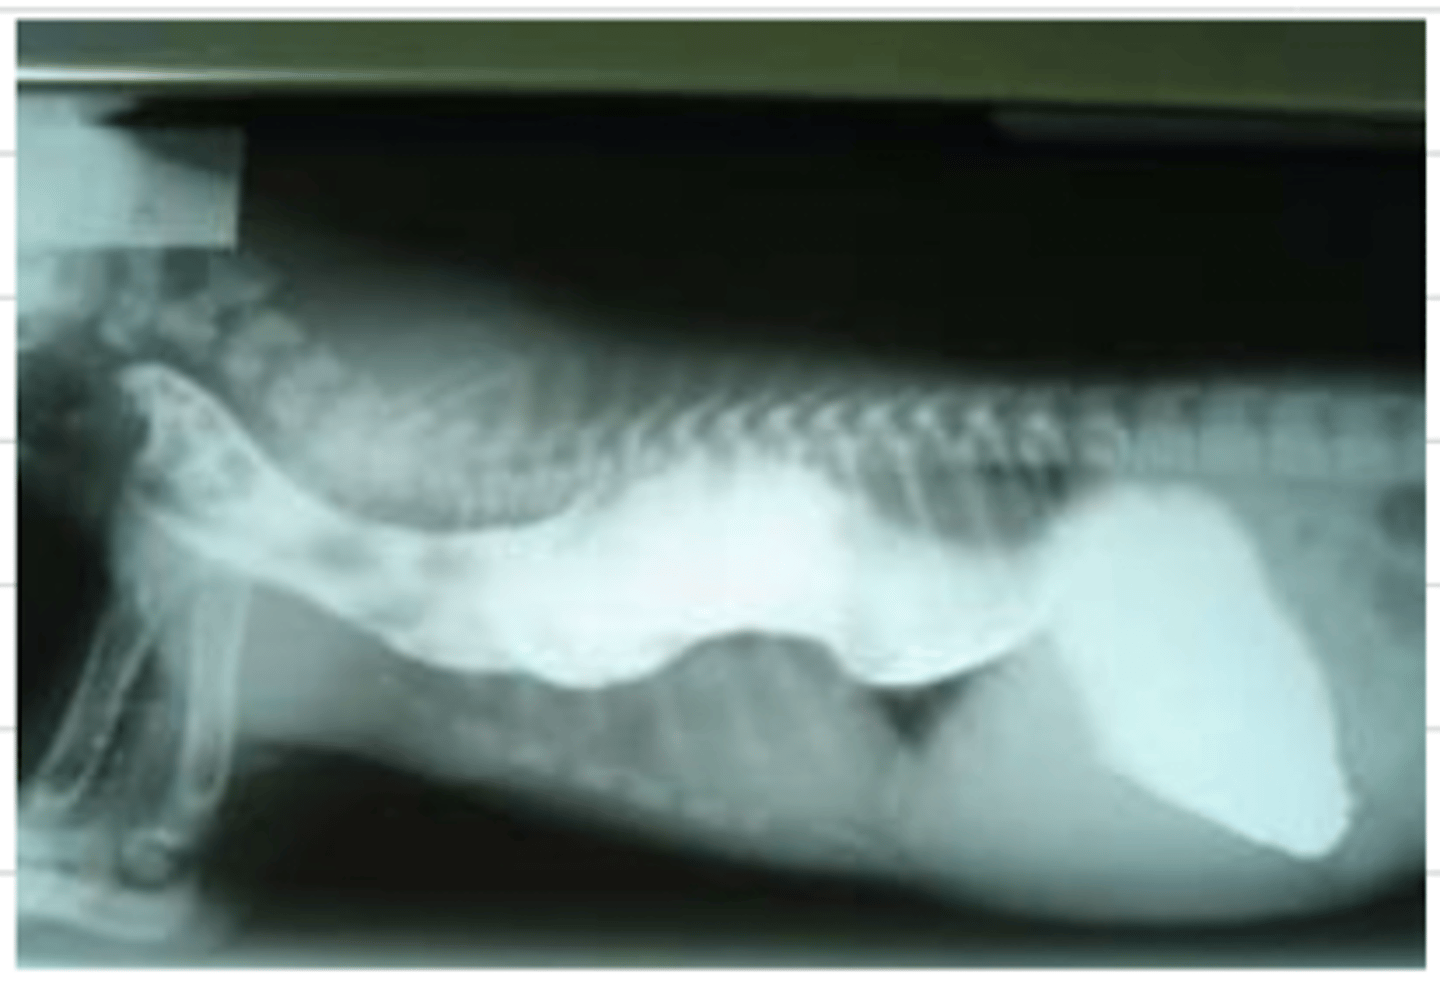

megaesophagus

after performing tests on this animal, we receive this image- what is the diagnosis?